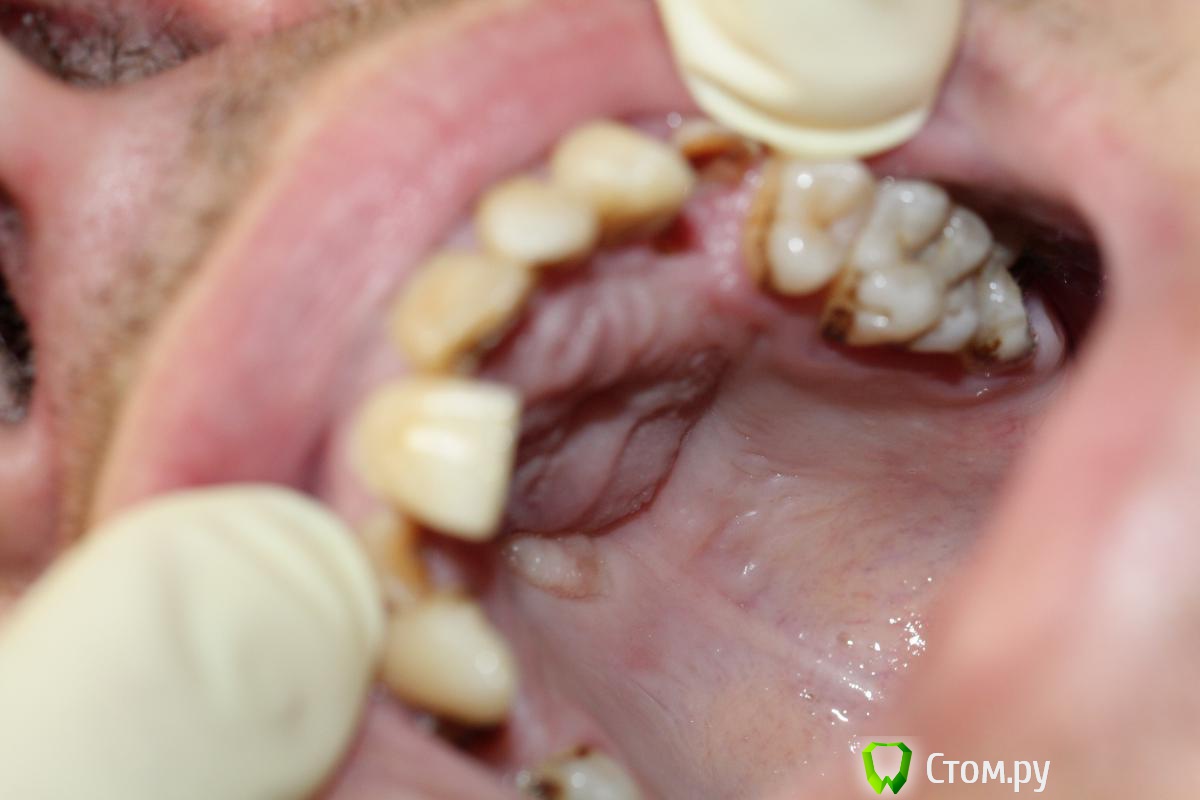

BryanDoc Опубликовано 5 февраля, 2014 Поделиться Опубликовано 5 февраля, 2014 (изменено) Пациент 25 лет обратился в клинику с нагноившейся кистой верхней челюсти слева, абсцесс передней трети твердого неба.На первом этапе проведено вскрытие абсцесса, после стихания острых явлений, установлена декомпрессионная трубка от системы с вестибулярной поверхности, и проверена витальность фронтальных зубов(Эндофрост), витальным оказался только 22 зуб, 21 и 11 зуб --апекс IRM, потом инжектор, 23-- инжектор, удалены корни 12, 24, 36 зубов проведена пародонтология, на последней КТ результат через 8 месяцев консервативного лечения.На начальном этапе подвижность 21, 11 была 3 степени, сейчас подвижности нет.У меня возник вопрос по поводу происхождения кисты? Подозрение что это носо-небная киста, по нескольким критериям---1--отклонение корня 21 зуба, располагается между 11 и 21 , и при эндодонтии 21 и 11 зубов было слизистое отделяемое в канале зубов из кисты.Доктора кто что думает на этот счет?так как дальнейшая тактика если это все таки носо-небная киста то это цистэктомия, через некоторое время. Изменено 5 февраля, 2014 пользователем BryanDoc Ссылка на комментарий

M@estro Опубликовано 6 февраля, 2014 Поделиться Опубликовано 6 февраля, 2014 (изменено) Я тоже так подумал, но 21 и 11 зуб без кариозных полостей и пломб, а пульпа в них была мертвая, точнее небыло уже к моменту раскрытия зуба. ну скол же на 21 ; вероятнее всего травматического генеза. Изменено 6 февраля, 2014 пользователем M@estro 1 Ссылка на комментарий

kriokov Опубликовано 6 февраля, 2014 Поделиться Опубликовано 6 февраля, 2014 так как пациент отметил что удар по этой группе зубов действительно был, но за 1 месяц до обращения в нашу клинику думаю , что еще одна травма была многим раньше , уж больно положение центрального резца характерно-- косо, вестибулярно, и зенит выше чем у 11, вряд ли из за кисты он так подвинулся. Пациент может и не помнить про травму толком. 1 Ссылка на комментарий